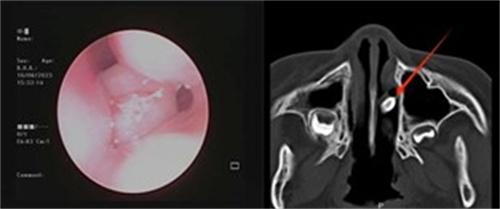

接診的李圓副主任經過仔細檢查,發現小朋友出現鼻塞的原因,并不是普通的鼻炎導致的,于是做了鼻腔內鏡的檢查,看見左鼻通道內有粘稠的膿性鼻涕,用吸引器將鼻涕吸走之后發現中后段有黃豆大小的新生物,為了確定物質的性質,李圓也讓患兒做了鼻腔內部的CT

考慮到小朋友年齡只有5歲,在配合程度上比較低,于是李圓立刻聯系麻醉,以及手術時把手術安排在第2天早上,10多分鐘便將手術順利完成,取出鼻腔內的異物后,發現是一個還帶著牙根的乳牙。